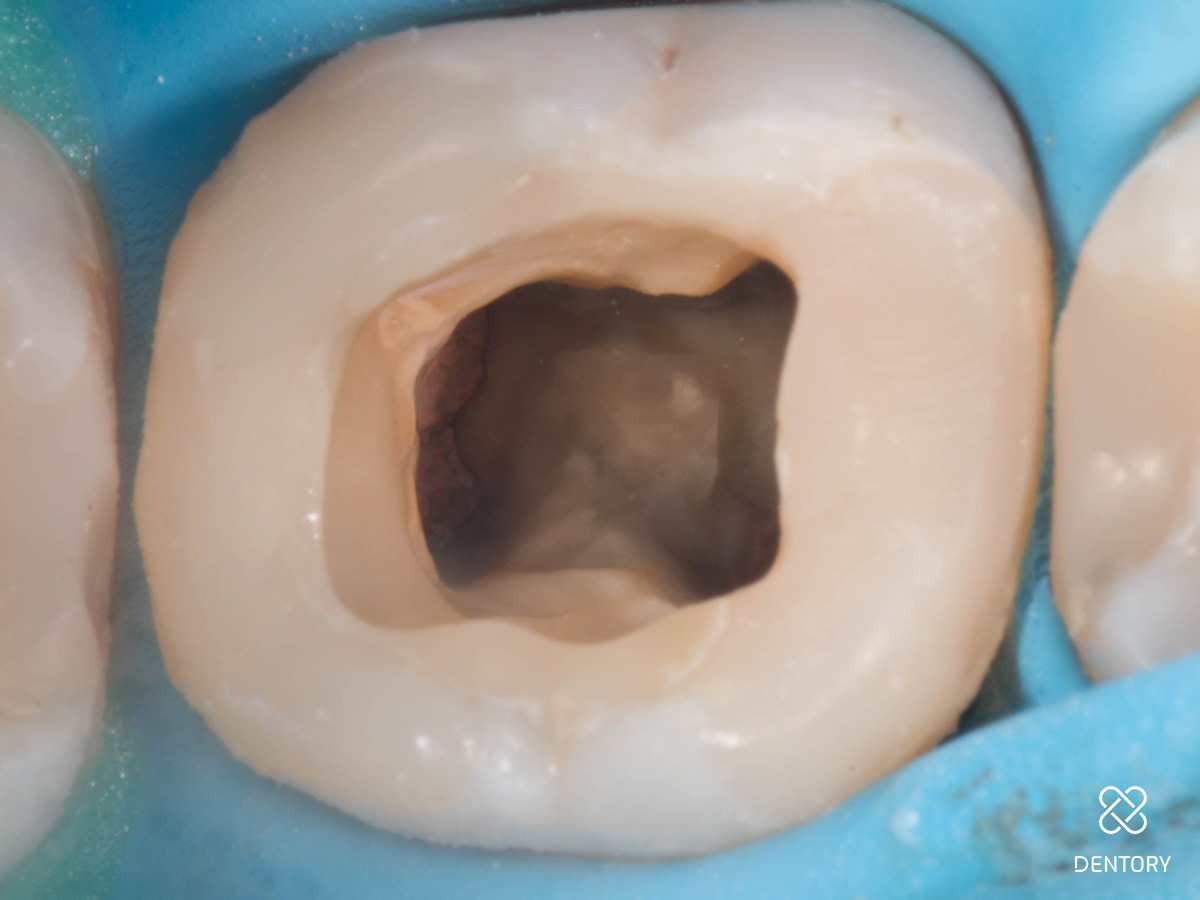

Abbildung 2

Entfernung der insuffizienten Füllung. Man kann erkennen, dass die Guttapercha aufgrund der hohen Transluzenz des damals verwendeten Materials durch die Füllung scheint.